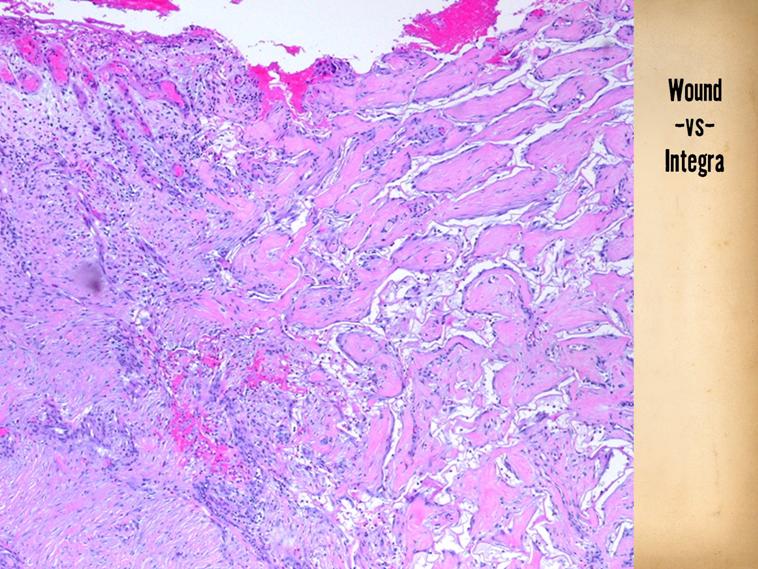

SLIDE SUMMARY:  At the late end of the spectrum (1 year after Integra), the differences between wound and Integra are still dramatic:  nearly normal looking dermis (right, Integra) versus contracted non-compliant scar.

------------------------------------------------------------------------------------------------------------------------------------

Another side-by-side of normal healing versus Integra, at the other end of the timeline.  Taken a year after Integra placement, The Integra (right) looks like normal dermis.  the conventional scar (left) is maturing, and developing some more normal dermal characteristics (fiber formation with interstices).  Yet the scar is what it is, highly collagenous, contracted, and apparently stiff.  (At bottom left are glomerular ghosts, as this reconstruction was done to close a large abdominal and flank defect, with multiple exposed viscera).